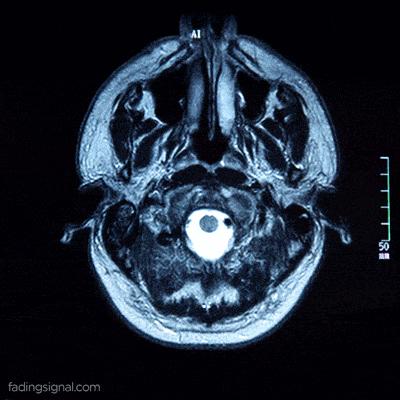

亞歷克斯出生時便被判了死刑,醫生預言她活不過六個月,因爲她的顱腔內幾乎空無一物。不僅是額葉、頂葉這些負責高級認知的大腦半球全都缺失,連視覺和聽覺中樞也蕩然無存。

據她父親描述,她顱內僅存的實體,是位於後部的一小塊小腦和腦幹,大小僅相當於成人的小指。這殘留的微小組織,即那勺“粉紅色果凍”,在傳統醫學視角下通常被視爲僅能維持心跳呼吸的生物殘渣。然而事實詭異得令人不安,亞歷克斯不僅活着,她還能感知。

2007年《柳葉刀》報道的那位法國男子,雖然腦室急劇擴張,但這實際上是慢性腦積水造成的物理壓縮。

他的大腦皮層並未消失,而是被壓成了一層薄紙貼在顱骨上(下圖),如同被壓扁的三明治,結構依然完整,神經連接依然存在。這證明的是大腦驚人的可塑性。

圖源:柳葉刀

而亞歷克斯的情況截然不同,她是真正的“缺失”,她的神經元不是被壓縮,而是被液化吸收殆盡。因此,亞歷克斯的生存比那位法國公務員更具顛覆性,她證明了人類可以在沒有皮層“硬件”的情況下,依然維持某種形式的“軟件”運行。